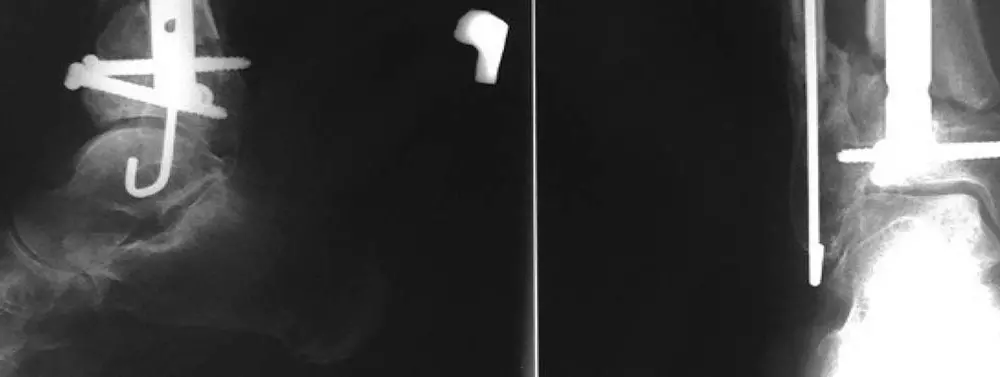

Wieloetapowe leczenie złamania otwartego II stopnia według Gustillo-Andersona końca dalszego kości podudzia typu „pilon” – analiza przypadku i krytyczna ocena zastosowanych metod

Mirosław Falis

Marcin Bęcki